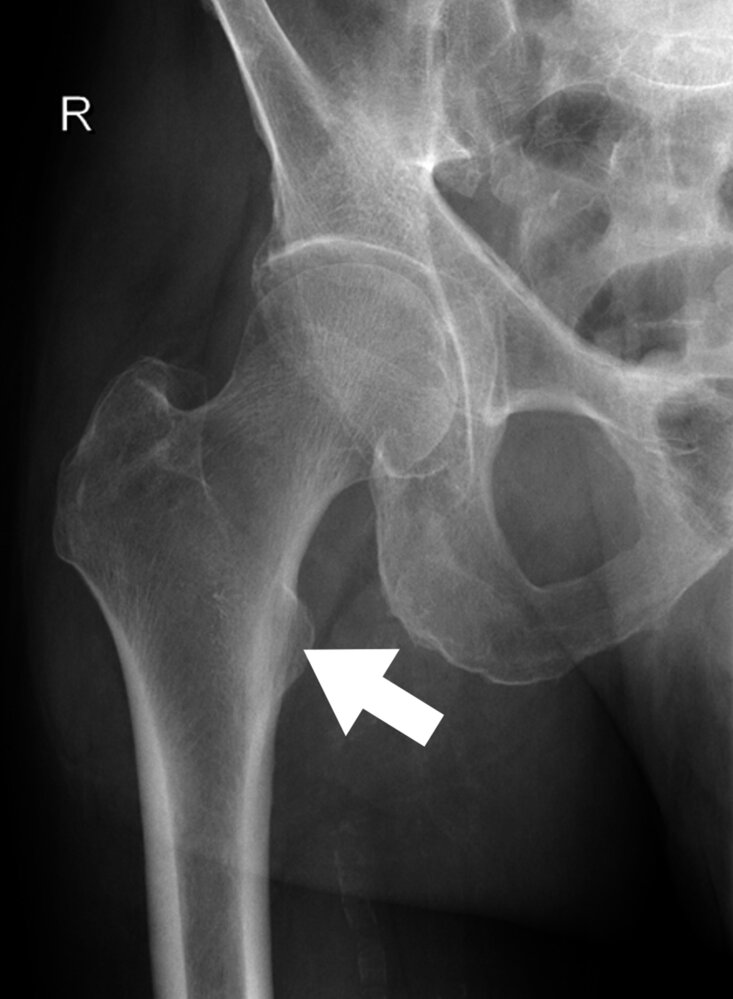

22. The X-ray image (anterior-posterior view) of a right hip joint included in the figure is marked with an arrow pointing to an anatomical structure.

Which hip joint movement is the muscle attaching to this structure primarily responsible for?

A. Flexion

B. Extension

C. Internal rotation

D. External rotation

E. Abduction